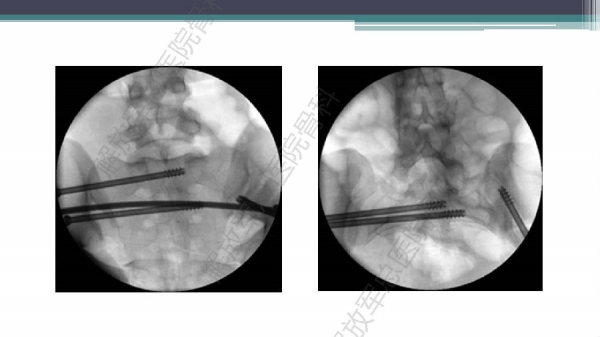

随着建筑和交通运输业的快速发展,合并骨盆、髋臼骨折多发伤、复合伤患者逐年增加,病死率和致残率都非常高。由于多发伤及复合伤、休克等往往不能在急性期对骨盆骨折进行确切复位及内固定,导致陈旧性骨盆骨折畸形愈合,从而产生一系列严重并发症,并且畸形矫正手术难度大、风险高、效果差。因此在抢救复苏后能不能尽早地、小切口甚至不切开、精确复位与固定骨盆骨折,防止陈旧性骨盆畸形愈合形成,成为广大骨科医生的挑战。解放军总医院创伤骨科在骨盆、髋臼骨折微创治疗方面做了一些工作,从微创理论探讨、到手术方法的改进,乃至钢板螺钉、微创复位器械等相继研发,形成了一系列的解决方案和配套内固定产品,为骨盆髋臼骨折的微创治疗奠定了基础。本幻灯则通过一例陈旧骨盆骨折畸形愈合的复杂治疗做引,通过介绍骨盆空间移位方式、透视特点、骨盆随意外架复位系统、复位原理以及1例典型病例的具体实施方案来综合、全面介绍我院微创骨盆髋臼骨折复位、固定新技术。